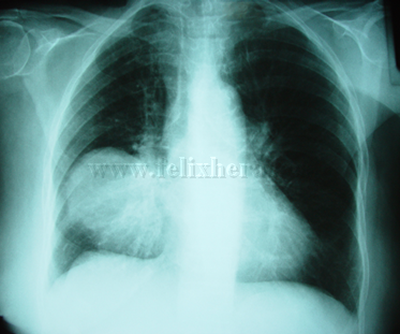

Mesotelioma fibroso pleural